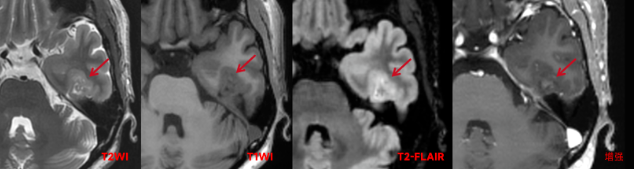

颅脑MRI癫痫序列:左侧颞叶内侧面脑回略肿胀,可见不规则小片状长T1稍长T2信号,范围约8x12mm,累及皮层,其内信号不均匀,可见斑点状短T1短T2信号及斑片状更长T2信号,增强扫描病变内可见多发斑点、小结节状强化灶。

影像诊断:左颞叶内侧面异常信号,考虑胶质神经元肿瘤-节细胞胶质瘤可能性大。